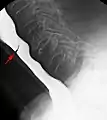

Esophageal web stenosis in barium swallow examination lateral view.

Esophageal web stenosis in barium swallow examination frontal view.